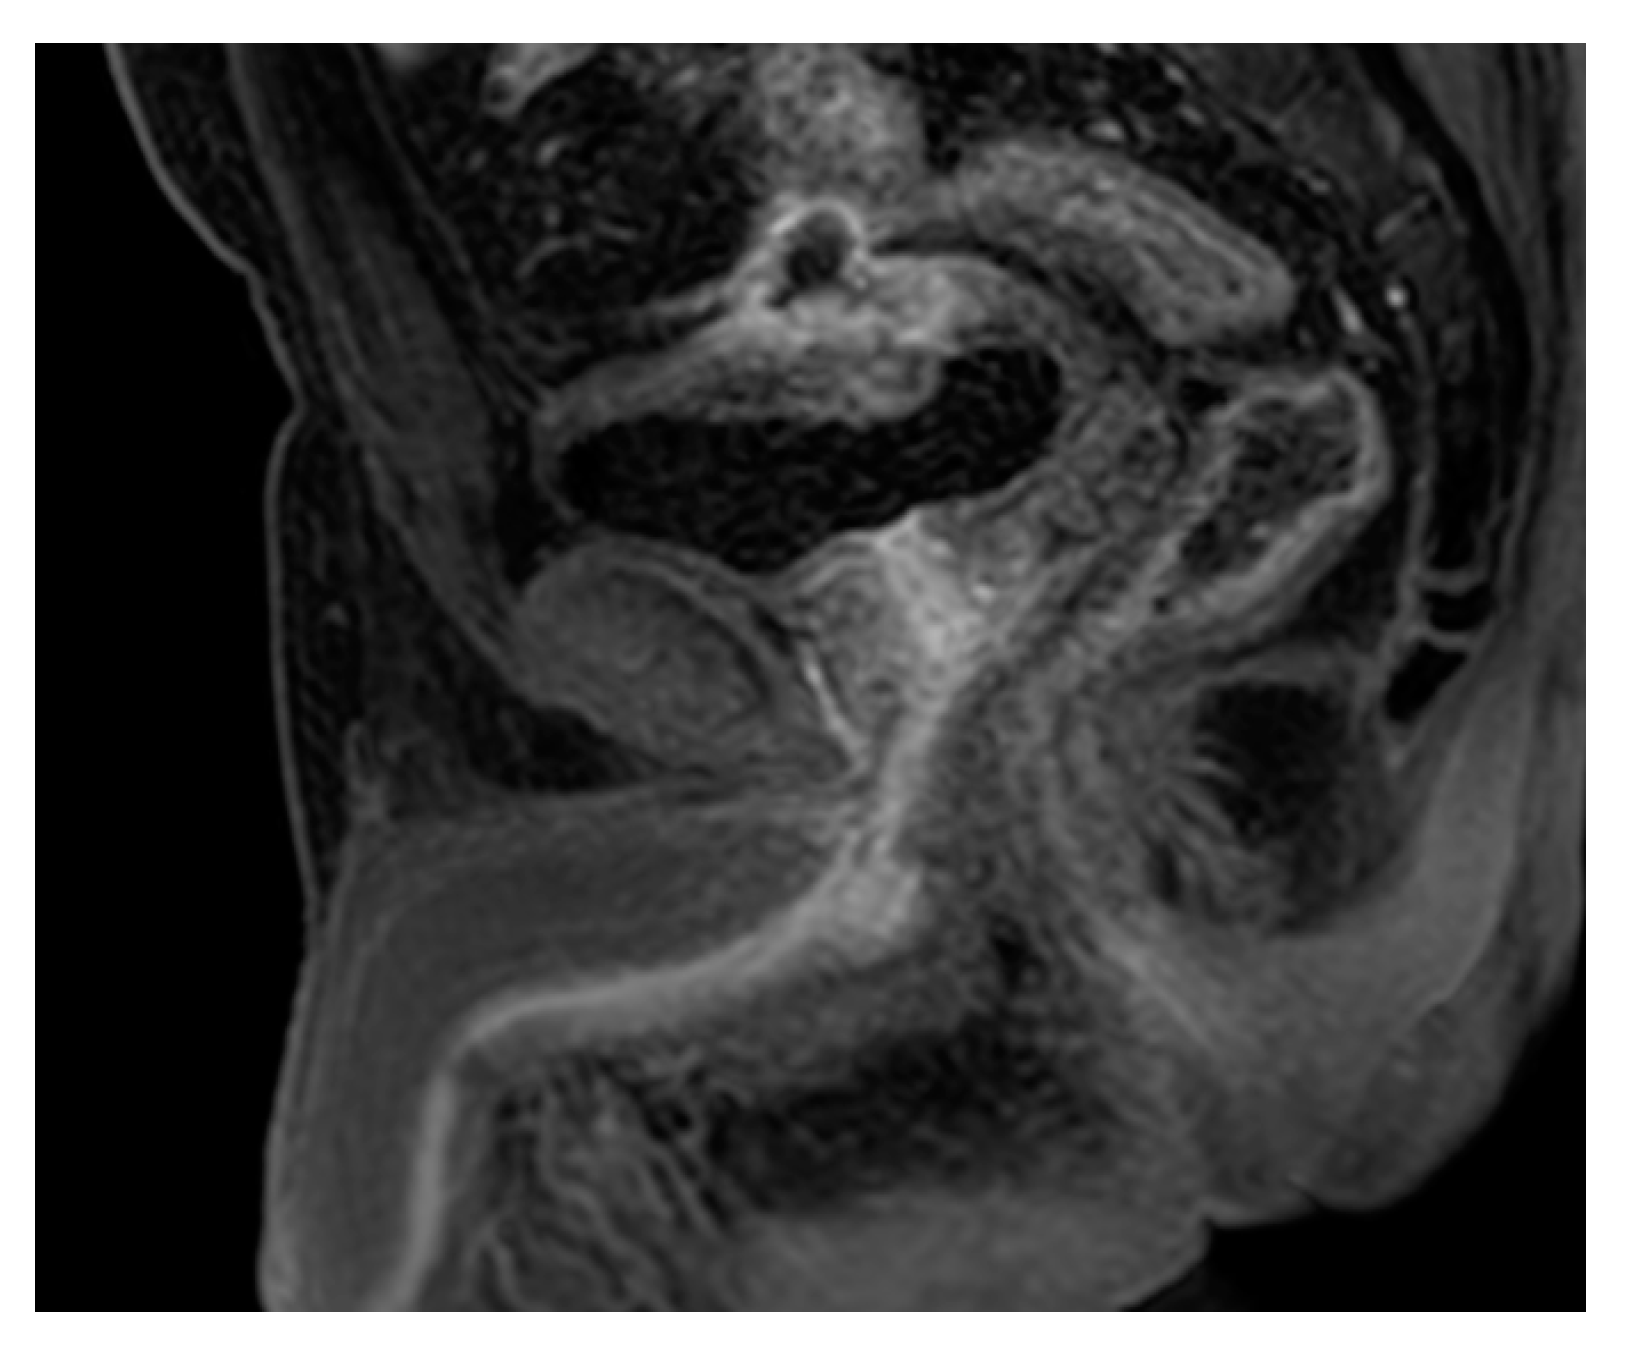

2.15. Acute Bacterial Prostatitis and Prostatic Abscess

| Prostatic abscess | Non enhancing fluid collection with peripheral or septal enhancement and non-enhancing central fluid. Possible extraprostatic extension |